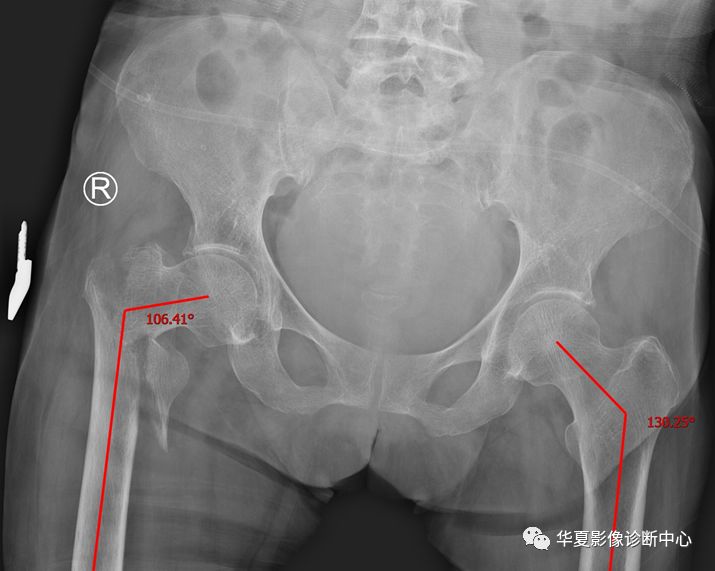

1、股骨颈干角:在髋关节正位片上,股骨干和股骨颈轴线的交角。 医学百科网 | YxBaike.Com

正常值110°~140°,大于140°,髋外翻,小于110°,髋内翻。 医学百科网 | YxBaike.Com